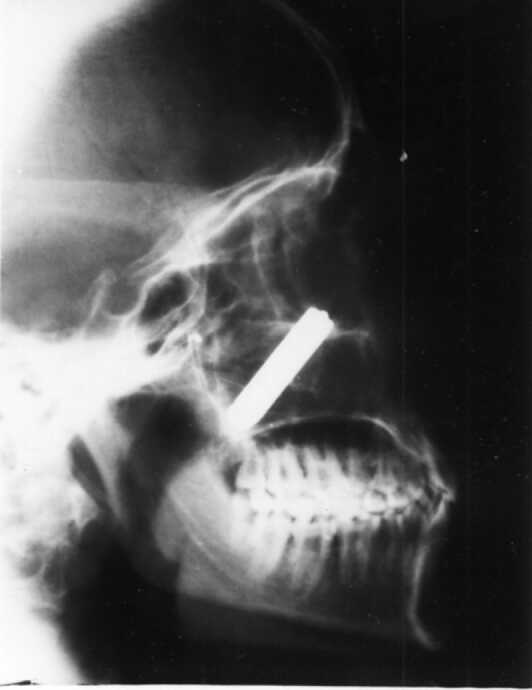

X-ray Paranasal Sinus revealed a radio-opaque shadow resembling a bullet abutting the medial wall of left maxillary sinus. All other walls of the antrum were intact.

Maxillary sinus is the largest of the paranasal sinuses and occupies the body of Maxilla. It is pyramidal in shape with base towards lateral wall of nose and apex directed laterally into the zygomatic process. It's roof is formed by the floor of the orbit and grooved by infraorbital nerve. The bullet fired from a distance of about four meteres entered the maxillary antrum through the medial canthus.

Thereafter it was found to be abutting the medial wall of maxillary sinus without causing damage to the structures medial to it i.e. middle and inferior meatus. While taking out the bullet, particular attention was being paid to the manner in which it was removed. The prongs of the forceps was covered with rubber tubes and thereafter it was pulled out. This is important because herein lies the legal responsibility of the surgeon.